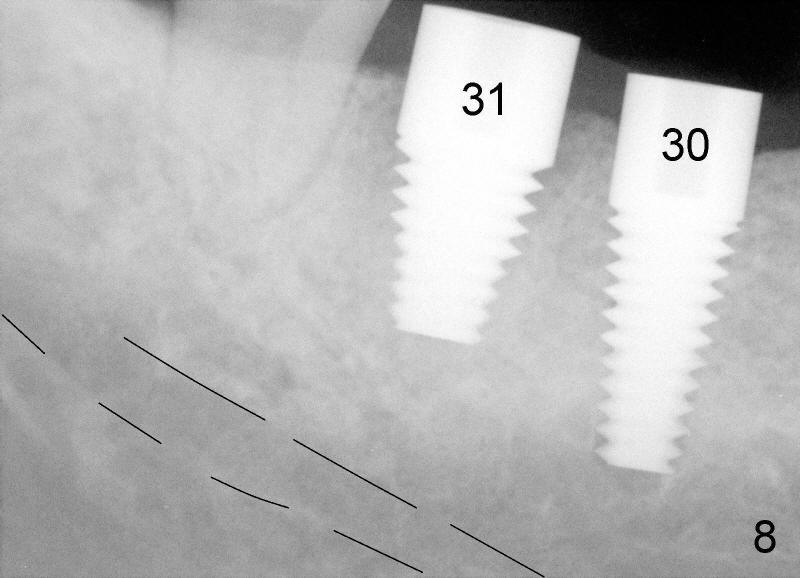

After adjustment, next drills (5x17, and 5x14 mm for #30 and 31) are located more appropriately relative to neighboring teeth (Fig.7) and also in some distance from the inferior alveolar canal (black lines). The septum of #31 is now distal to the drill for #31. Finally 6x17 and 7x14 mm Tatum tapered implants are placed with certain degree of initial stability (Fig.8). Black dashed lines represent the inferior alveolar canal. Fig.9 is taken immediately post-implant placement.